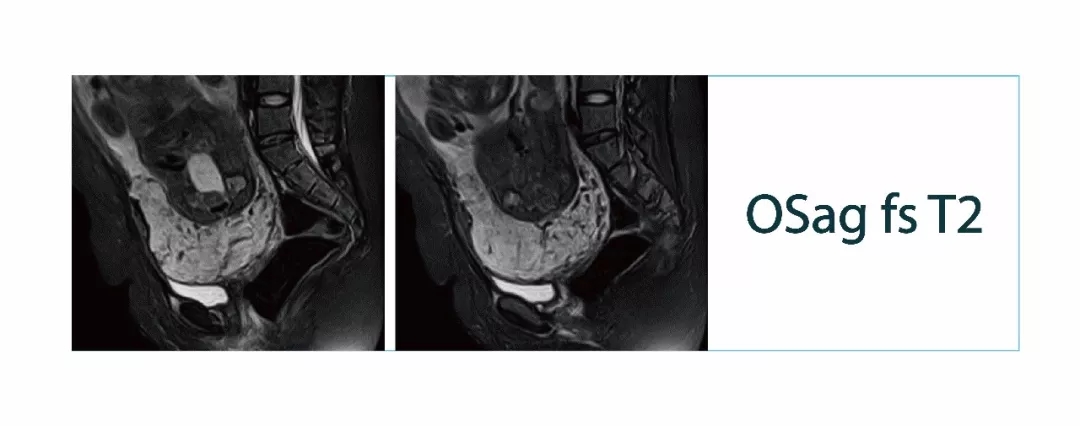

【朗润影像档案】20180302磁共振影像病例结果讨论